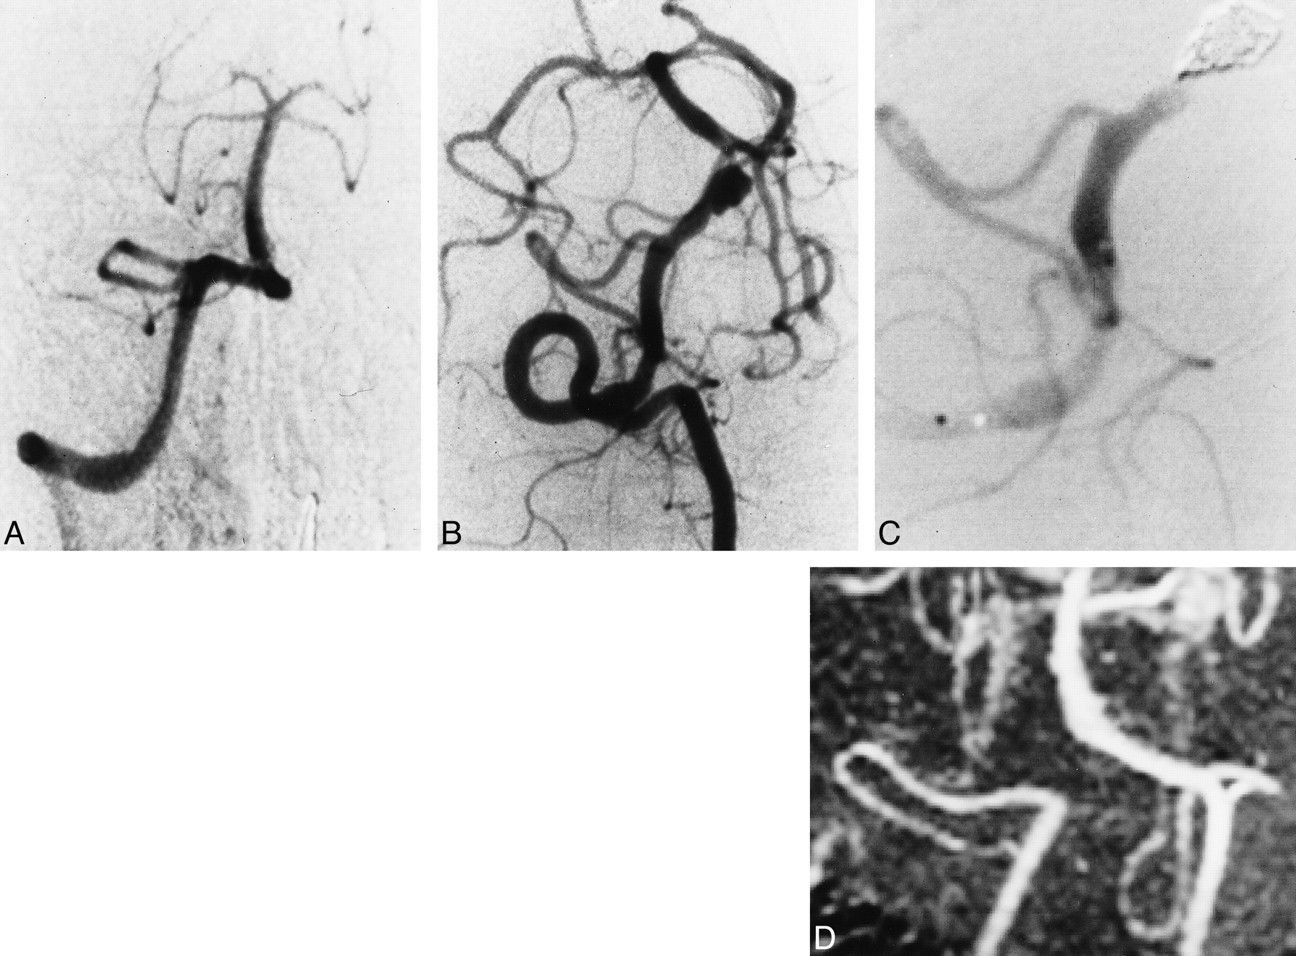

Case 2

A 55-year-old man had sudden onset of a headache followed by numbness of the right limbs, at which time he sought medical attention. Six hours after the onset of symptoms, he became comatose and experienced dyspnea during examination and was immediately transported to our emergency center. Neurologic examination on admission revealed a Hunt and Kosnik grade of V, and CT scans showed marked subarachnoid hemorrhage. An emergency four-vessel angiographic study showed no abnormal findings (Fig 1A) although a second, follow-up angiogram on day 7 showed a right vertebral artery dissecting aneurysm distal to the PICA origin (Fig 1B). After successful embolization (Fig 1C), the patient recovered gradually and was discharged with no neurologic deficit 3 months after symptom onset. Follow-up angiography 2 months after embolization showed complete occlusion of the dissection site, which was confirmed on follow-up MR angiograms 7 and 19 months after the treatment (Fig 1D).

Case 2.

A, Right vertebral angiogram on day 1, anterolateral view, shows no abnormal findings.

B, Follow-up right vertebral angiogram on day 7 shows a dissecting aneurysm in the vertebral artery, distal to the PICA origin.

C, Right vertebral angiogram immediately after embolization of the dissection site.

D, Follow-up MR angiogram 7 months after embolization.